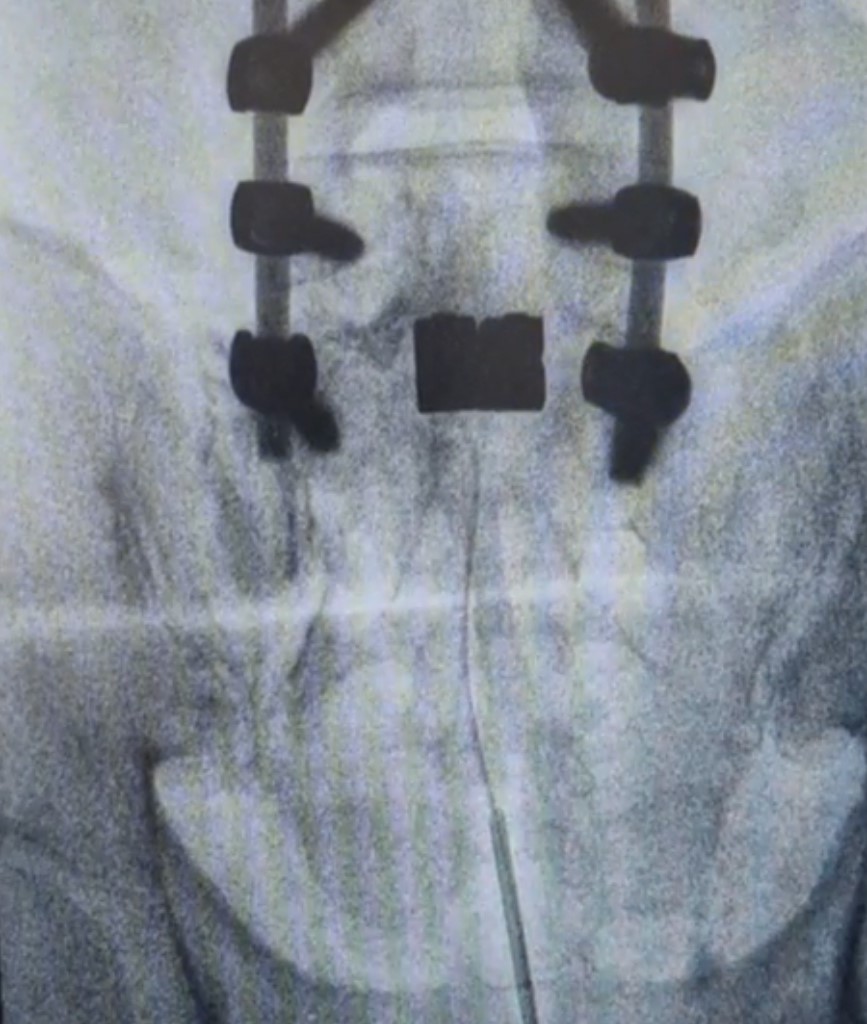

Πρόκειται για ελάχιστα επεμβατικές τεχνικές νευροτροποποίησης, δηλαδή αλλαγής του τρόπου αντίληψης του επώδυνου ερεθίσματος. Αυτό γίνεται με εμφύτευση ηλεκτροδίων επισκληριδίως (επισκληρίδια νευροδιέγερση) ή υποδορίως (περιφερική νευροδιέγερση) ανάλογα με την κατανομή του μετεγχειρητικού άλγους.